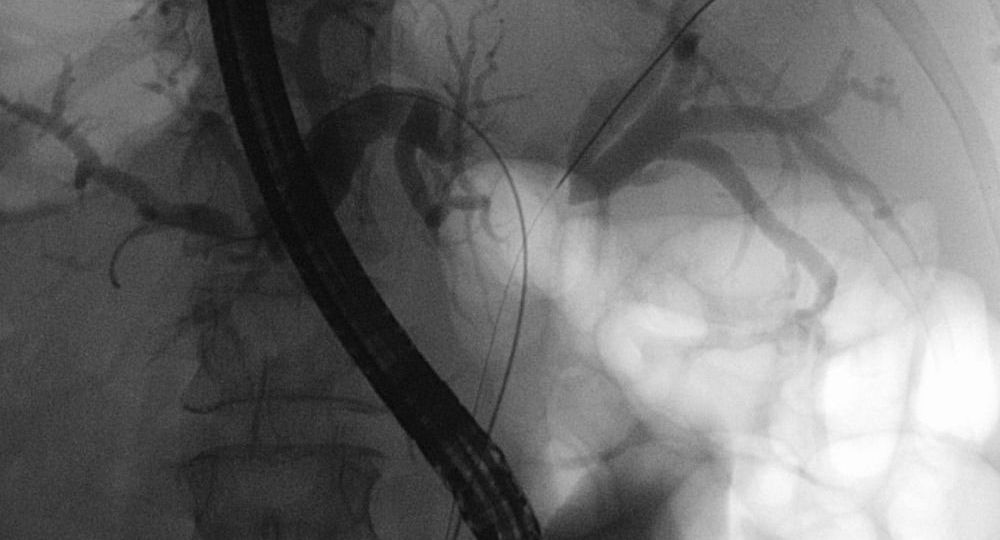

- Imaging: Imaging techniques such as ultrasound, CT scans, MRIs, and PET scans are essential for identifying the tumor’s location and assessing whether it has spread to nearby structures or distant organs.

- Endoscopic retrograde cholangiopancreatography (ERCP): This procedure can help diagnose blockages in the bile ducts and provide biopsy samples to confirm the presence of cancer.